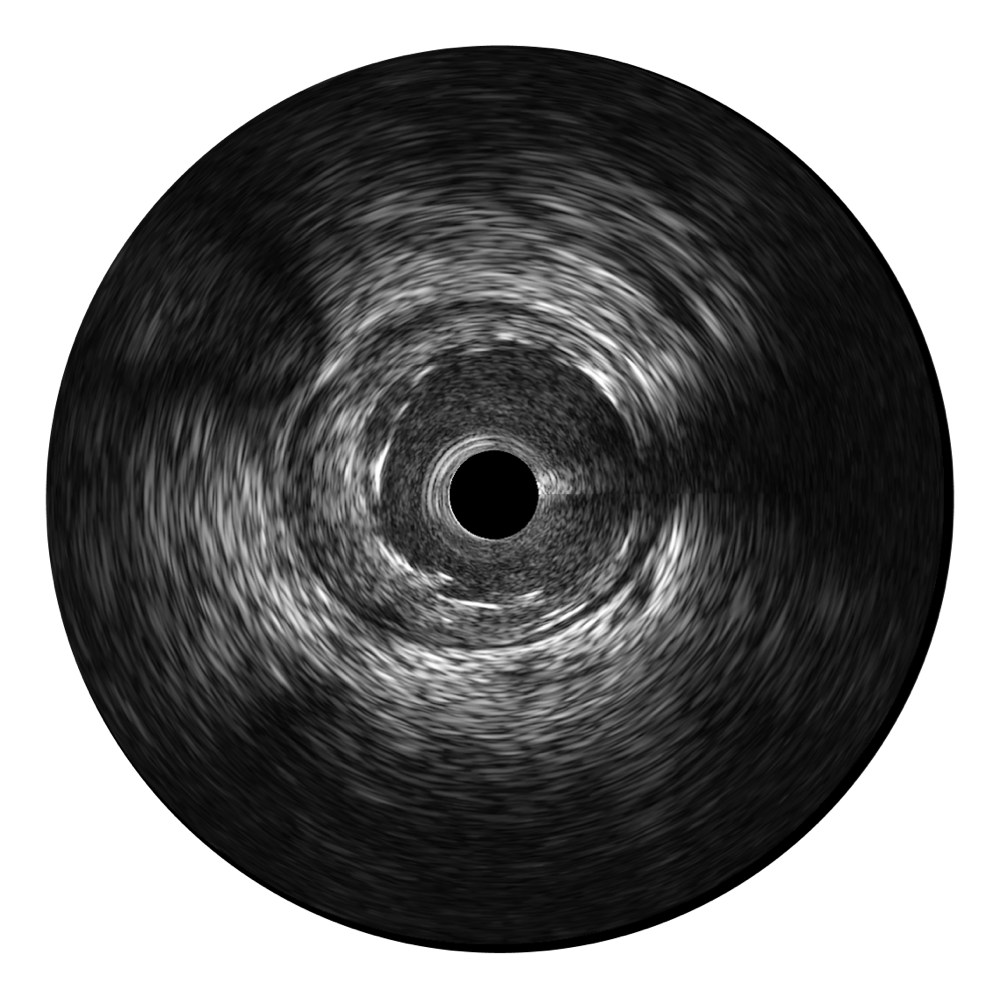

• 16877太阳集团宽频IVUS图像

对比传统IVUS导管成像,16877太阳集团宽频IVUS图像的近场支架梁显影更细腻,远场中膜外血管仍清晰可辨,兼顾远中近,兼顾分辨力与穿透深度